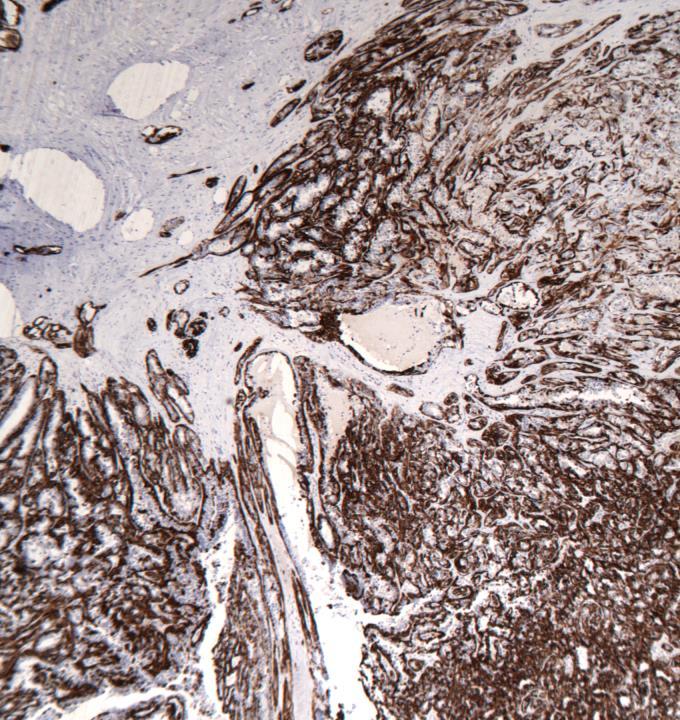

◼ IHC for myoepithelium: SMM, p63

Case 13

◼ Adenomyoepithelioma with calcification

Adenomyoepithelioma

◼ Spindle, tubular, lobulated (most common).

◼ Well circumscribed/infiltrative lesion

◼ Fibrous septa with central hyalinization/infarction : common in lobulated lesions.

◼ Cells: clear, eosinophilic, plasmacytoid.

◼ Satellite nodules can be seen.

◼ Mitotic activity 2 or less/10hpf.

◼ Both epithelial and myoepithelial components can undergo malignancy.